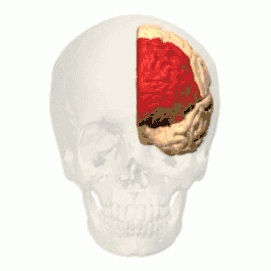

Prefrontal cortex

The prefrontal cortex (PFC) is responsible for complex cognitive behaviour, decision making and consciousness (Burton, Westen, Kowalski, & Westen, 2015). While there is still much debate as to what specific role the different areas of the PFC play in anxiety related disorders, a review conducted by Spalding in 2018, investigated the role that the medial prefrontal cortex (mPFC) has in relation to fear generalisation - conditioned fear generalising to related stimuli, (Spalding, 2018). The study found that in human subjects, the ventral mPFC plays an important role in inhibiting the fear generalisation, while dorsal mPFC is seen to activate fear generalisation. Studies indicate that "higher levels of anxiety have been associated with increased activity in the dorsal mPFC (Straube et al., 2009), but further research needs to be done to investigate this.